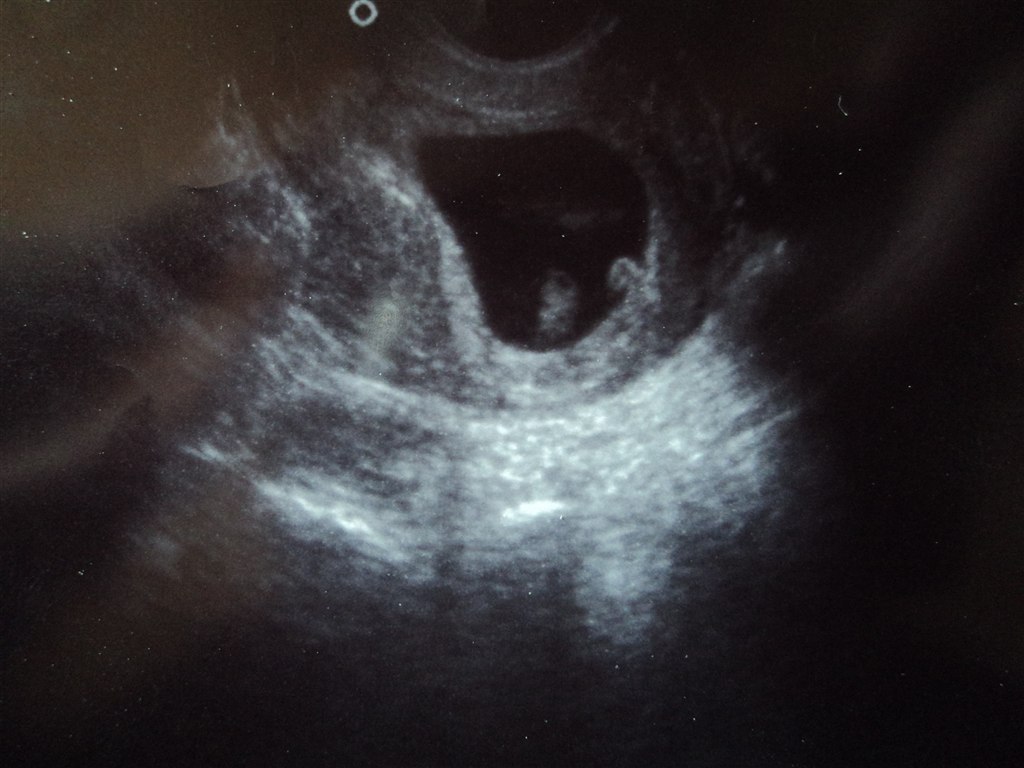

alt så fint ud, og lille blyp blev rykket 3 dage tilbage, så jeg skulle være 6+5. men der var masser af hjerteblink og nu er jeg bare super lettet

Vedhæftede fotos (klik for at se i fuld størrelse)

Tillykke, jeg er også 6+5 idag, så været til scanning idag